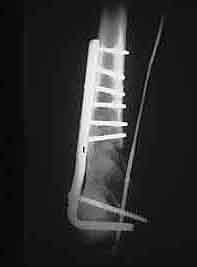

An initial injury film shows a closed supracondylar femur fracture with an arteriogram done for questionable signs of arterial injury showing a nonocclusive intimal flap of the popliteal artery. Since this arterial injury fit the published criteria for nonop observation, our orthopedic surgeons went ahead and did ORIF. 6 weeks later a F/U angio shows complete resolution of the intimal flap -- unnecessary surgery thus avoided.

This illustrates the RULE for nonocclusive arterial injuries, NOT the exception.